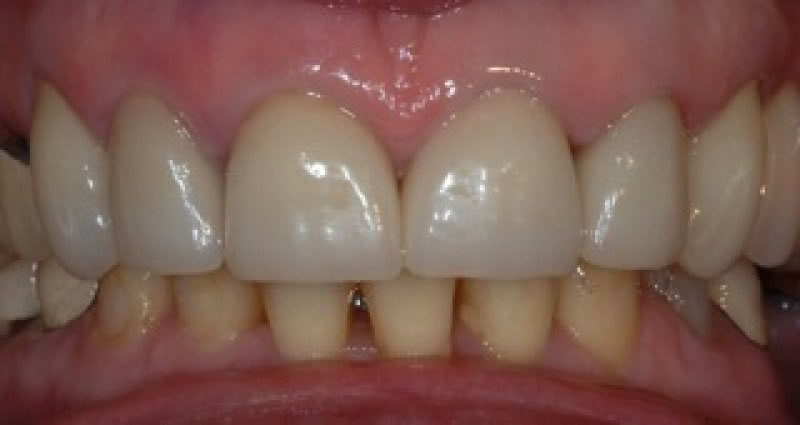

Made from porcelain or ceramic, the new crown will be styled and coloured to match the rest of the patient’s existing natural teeth.

Case Studies

Dental Crowns (7 images)

Upper crowns and lower composites (4 images)

Dental Crown work ( 2 images)